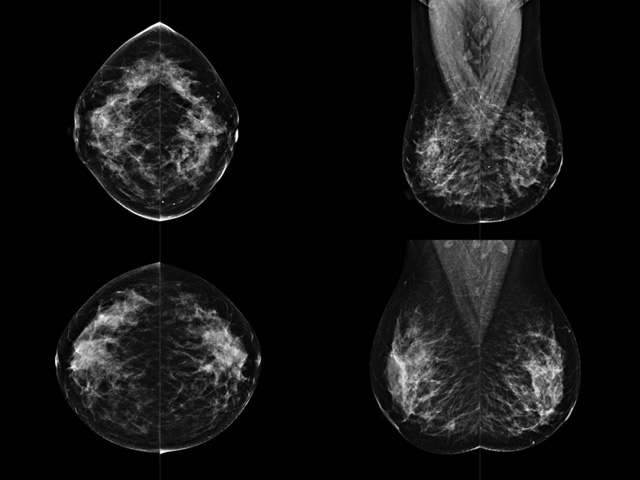

乳房檢查時(shí)候要注意一些細(xì)節(jié),需要更深入的了解這樣才能使檢查更準(zhǔn)確。乳腺DR是乳腺癌的篩查診斷工具設(shè)備。是乳房方面檢查的重要影像方法。它可以臨床檢查出早期的乳腺癌。可以判斷良性惡性。因?yàn)樗梢詸z查出早期的病變。對(duì)良性惡性檢查的準(zhǔn)確率達(dá)到90%以上。發(fā)病高峰年齡為45歲到54歲。50歲檢查出來乳腺癌病患,可以讓死亡率下降3成。所以30-40歲女性每年做一次乳腺DR檢查。40歲以上就一年兩次。如果家族史有乳腺癌的30歲以下也需要做檢查。清晰顯示乳腺各層組織嚴(yán)重的乳腺增生,乳腺炎,乳腺外傷也建議1年檢查一次。極大提高了早期乳腺癌的敏感度和診斷率。

大角度、高質(zhì)量的乳腺檢查,可以讓女性帶來身體健康安全。為醫(yī)生提供了高清影像數(shù)據(jù)。乳腺檢查時(shí)候各個(gè)部位影像顯示出來。白色乳腺導(dǎo)管跟纖維結(jié)締組織。模糊的是脂肪。病變一般是不透明的白色。有需要放大來檢查。乳腺DR沒有重疊偽影。輻射劑量更少。因?yàn)槿橄侔┌l(fā)病每年都有所提高,對(duì)女性都造成了嚴(yán)重的身體健康危害。早做檢查早治療是不可忽視的舉措。可以大大的降低死亡率。保證身體健康。一般檢查避開經(jīng)期,來完7天左右是最佳的檢查時(shí)間。絕經(jīng)的女性就沒有要求。孕婦不參加乳腺DR檢查, 6個(gè)月內(nèi)準(zhǔn)備妊娠的婦女也不宜行此檢查。